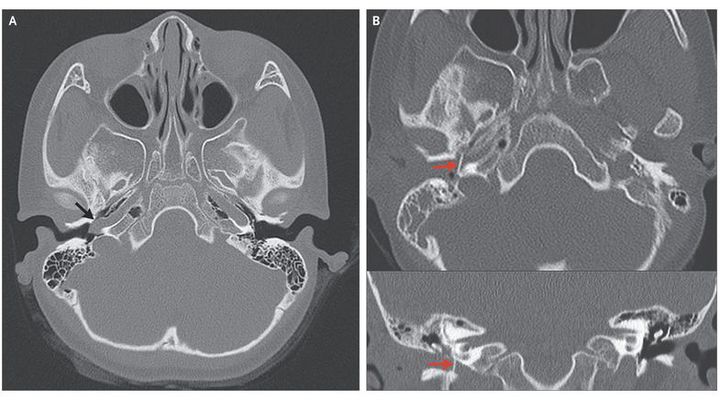

A 6-year-old girl presented with a 1-year history of pulsatile tinnitus in her right ear. Pure-tone audiometry showed normal hearing. Otoscopy showed a whitish pulsatile mass behind the tympanic membrane in the anteroinferior quadrant of the middle-ear cavity (see video). Computed tomography (CT) of the temporal bone revealed a vessel coursing through the hypotympanum (Panel A, arrow) and entering the carotid canal through a dehiscence in the carotid plate — a finding consistent with an aberrant right internal carotid artery. Normal structures in the left ear are shown for comparison, including the normal location of the internal carotid artery at this level within the carotid canal and an intact carotid plate. An aberrant internal carotid artery in the middle ear is a rare vascular anomaly. It is essentially a collateral pathway that traverses the middle ear, involving the communication of an enlarged inferior tympanic artery with an enlarged caroticotympanic artery, and can occur when the cervical internal carotid artery is underdeveloped or has regressed during embryogenesis. An aberrant internal carotid artery can mimic other middle-ear lesions, so it is important that imaging be performed before any surgical intervention in order to avoid bleeding complications that may result from misdiagnosis. The patient underwent surgical correction (Panel B, arrows; the upper panel shows an axial CT scan, and the lower panel a coronal CT scan). At 13 months of follow-up, otoscopy showed a healthy tympanic drum, and the patient reported no remaining symptoms.